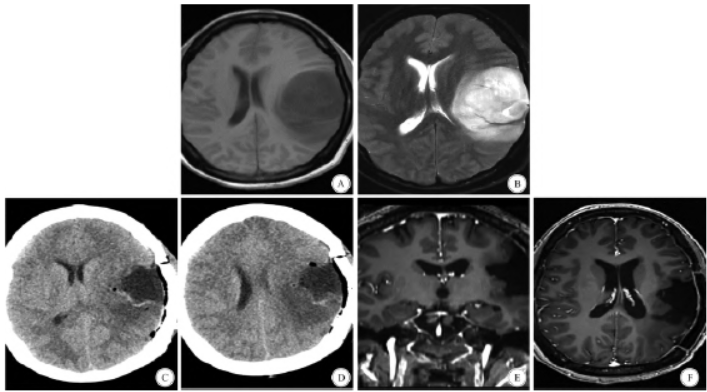

(magnetic resonance imaging,MRI)检查示,左侧颞顶叶见团块状T1 WI 高信号影,T2 -FLAIR 呈相对稍高信号影,弥散加权成像(diffusion weighted imaging,DWI)呈不均匀高信号,相应表观弥散系数(apparent diffusion coefficient,ADC) 图信号局部稍减低,大小约55 mm ×46 mm ×57 mm,病变周围见片状T1 WI 高信号,T2 WI 高信号,周围脑组织受压,考虑高级别胶质瘤(图1)。

(temozolomide,TMZ)化疗等Stupp 方案治疗。随访至2024年4 月17 日,复查颅脑MRI 肿瘤无复发(图1),患者一般状况良好,无进展生存期超过13 个月。

图1 患者影像结果。A:入院时,T1 加权成像在左侧颞顶叶发现高信号、边界不清的病变; B:入院时,T2 加权成像在左侧颞顶叶检出高信号和边界不清的病变; C、D:术后第1 天,CT 显示左侧颞顶叶肿瘤被切除; E:术后13 个月,左颞顶叶斑片状低信号强度,T1 加权成像无明显信号增强(冠状面); F:术后13 个月,T1 加权成像无明显增强(轴状面)